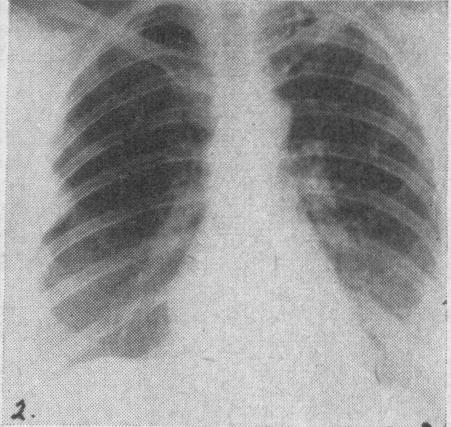

Intra-thoracic haemangioma of the chest wall.